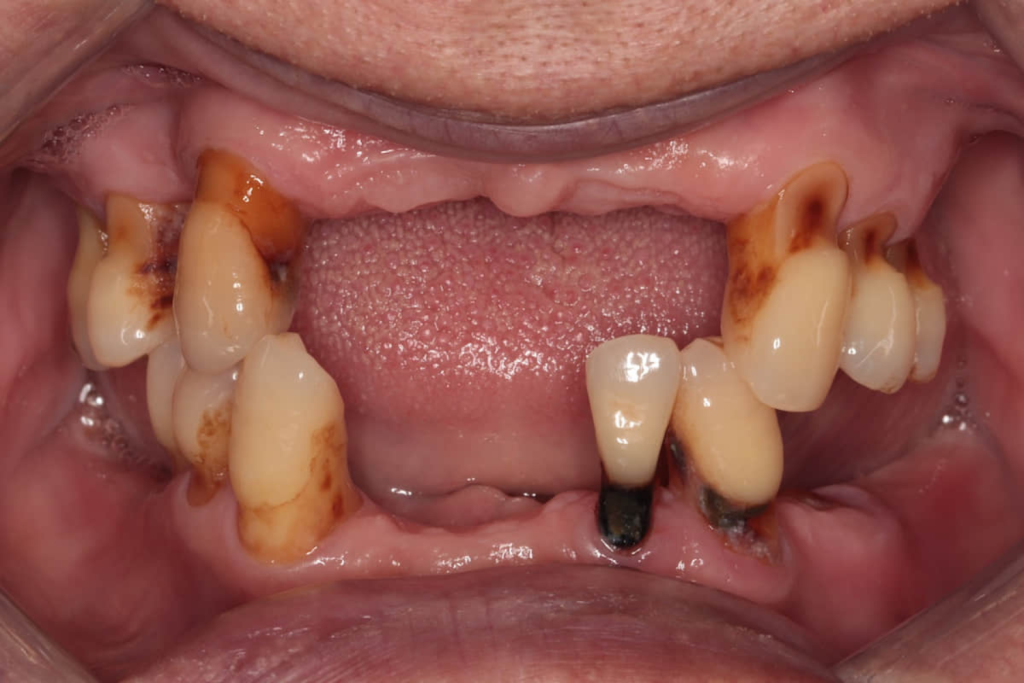

術前口內照